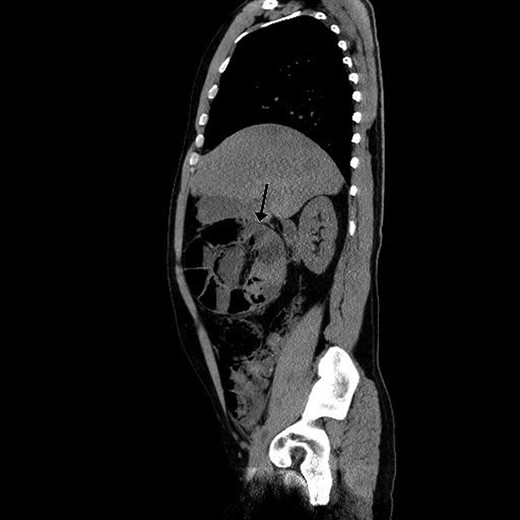

Paraclinical tests showed leucocytosis (10,1 × 109/l) and normal serum lactate. A computed tomography (CT) scan showing gastric retention, encapsulated dilated small intestines in the right upper quadrant with pneumatosis intestinalis and collapsed small intestines distally from this area interpreted as intestinal obstruction (Figs 1 and 2).

Coronal view of preoperative abdominal CT scan demonstrating encapsulated dilated small intestines in the right upper quadrant with pneumatosis intestinalis.